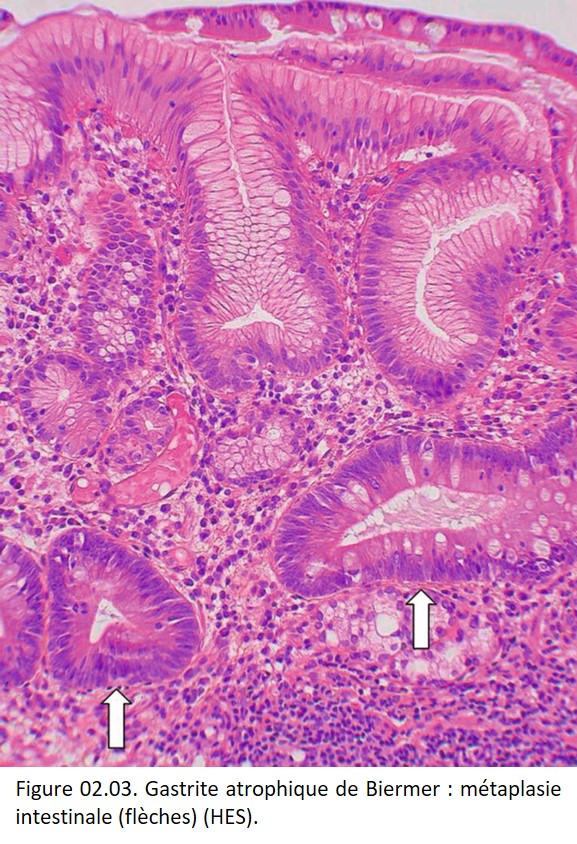

• Contexte physiologique : métaplasie déciduale du chorion cytogène de l'endomètre ;

• Contexte pathologique : une métaplasie intestinale de l'épithélium gastrique (Gastrite atrophique de Biermer) (figure 02.03) ; une métaplasie glandulaire d'un épithélium malpighien (œsophage de Barrett) (figure 02.04) ; une métaplasie malpighienne de l'épithélium glandulaire bronchique ; une métaplasie malpighienne de la muqueuse glandulaire endocervicale du col de l'utérus.